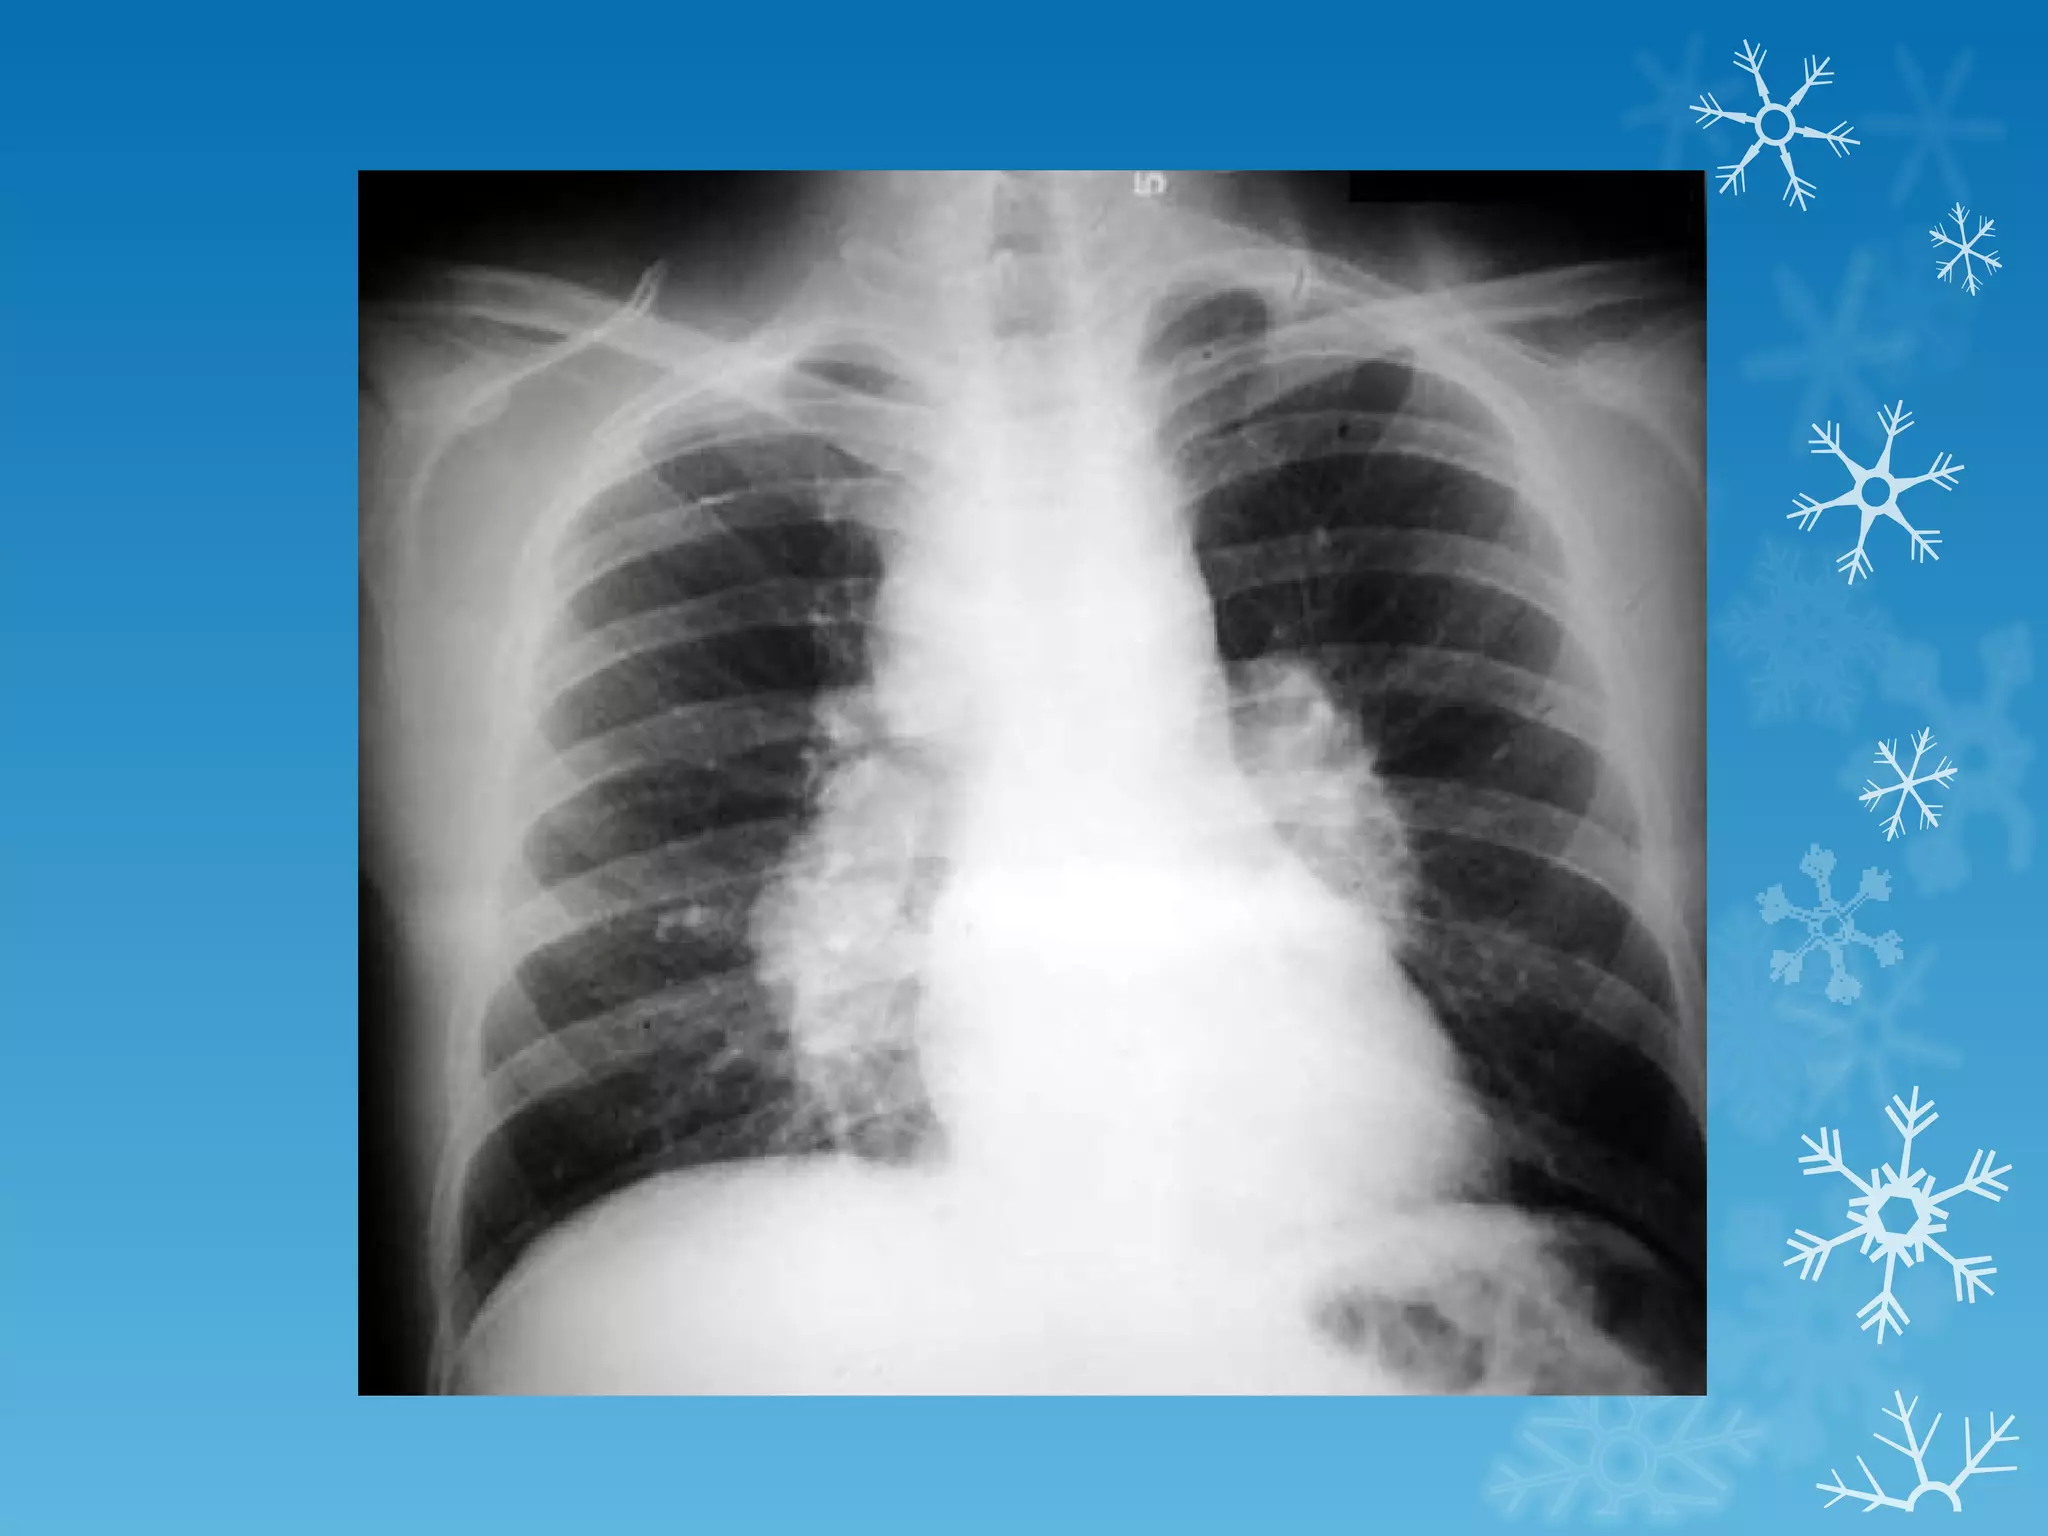

This document discusses chest x-ray interpretation and provides guidance on evaluating x-rays. It explains that tissue density determines how an x-ray beam penetrates, with denser tissues appearing whiter and less dense tissues appearing blacker. It also outlines different chest x-ray views and factors to consider like patient orientation, age, gender, and rotation. Abnormalities are described as appearing too white, too black, too large, or in the wrong place. The document stresses a systematic approach of identifying, localizing, describing lesions, and providing differential diagnoses.